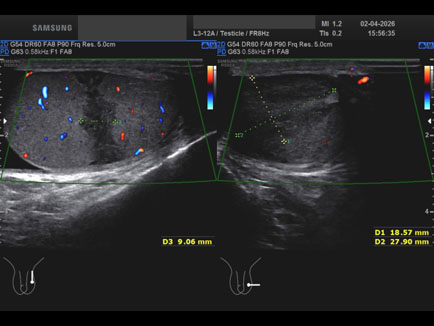

Data inserimento: 07/04/2026

Ecografia del: 02/04/2026

Strumento: Samsung

Sonda: Lineare

Età Paziente: M

Commento all'esame: lesione infartuale del didimo sn dopo intervento per varicocele.

Conclusioni: lesione infartuale del didimo sinistro (Segmental Testicular Infarction - STI).

Realizzazione: Dr. F. Pietro Tarini - Gubbio (PG)

Presentazione: Dr. Massimo Dolciotti - Ancona

Elaborazione digitale: Andrea Dini - Ancona